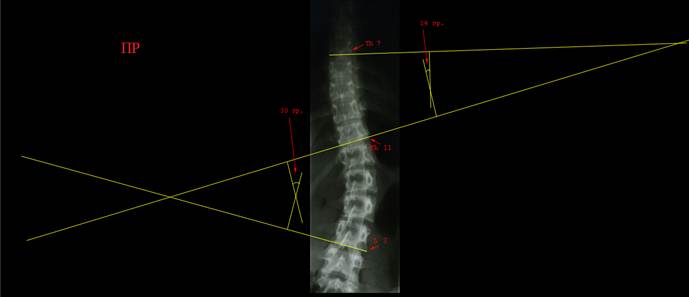

Прямая

рентгенограмма позвоночника ребенка 14 лет, сколиотическая деформация в грудном

и поясничном отделе компенсированная, S –

образная, выражена ротация позвонков. На

первом рисунке выполнен поиск нейтральных позвонков при помощи линий. На

практике так не делают, множество линий мы провели для наглядности примера.

Красными стрелками обозначены позвонки, линии которых дали максимальный угол

при пересечении. Вы видите, что найти эти позвонки будет не так уж трудно и без

множества линий. На следующем рисунке лишние линии убраны и проведены

перпендикуляры к линиям нейтральных позвонков. Красными стрелками обозначены

углы дуг (углы по Коббу). Угол основной дуги составил 30°, компенсаторной

- 14°. Деформация достаточно серьезная, это третья степень.